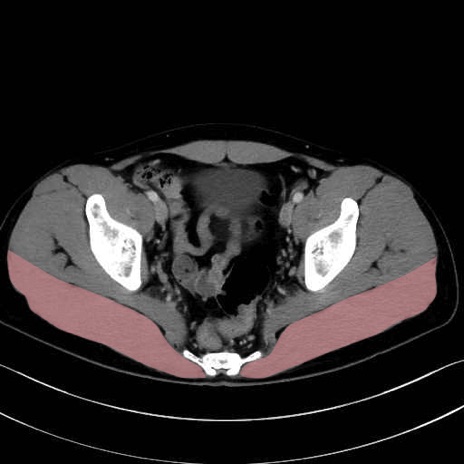

大殿筋 (Gluteus maximus)